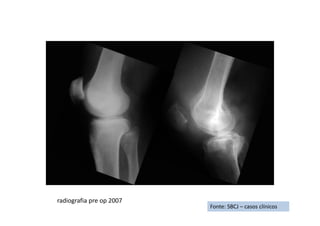

RX de Frente

Fonte: SBCJ – casos clínicos

RX de Perfil